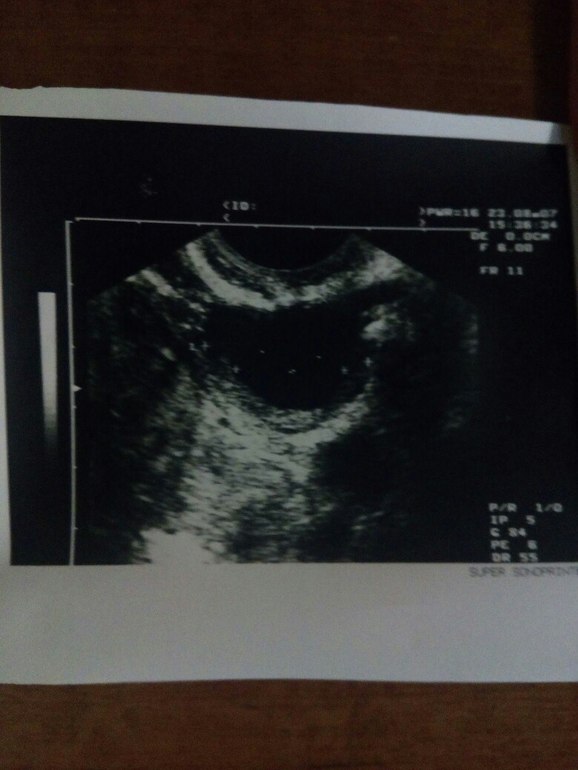

24.08.17 решила сходить на узи, как раз 15 день цикла (цикл у меня 29-33 дня), вроде бы как овуляция должна быть. Сходила и вышла в шоке.... оказывается доминантных фолликулов нет, да еще и киста. Узист сказал срочно к врачу ибо яичники мои не работают.

Вот такое заключение и собственно фото мойе кисты.